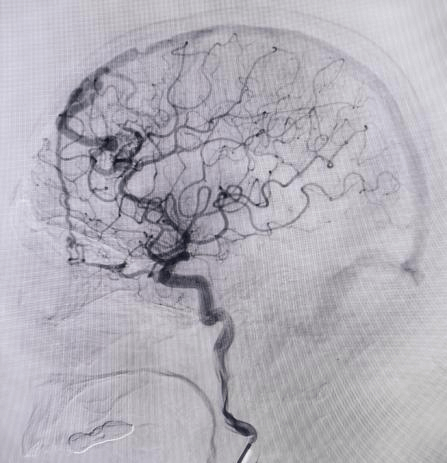

另一位烟雾病患者,5个月前因脑出血查出双侧烟雾病,在外院治疗。3个月前,为进一步治疗烟雾病,遂来我院,由于出血在右侧,医疗中心吴鹏副院长率领团队为其先行右侧烟雾病搭桥手术。手术精细复杂,需要将头皮动脉血管与脑表面血管精准缝合,恢复脑部血供。术后患者恢复满意,此次再次来行左侧烟雾病搭桥手术。每一步治疗,都根据患者病情变化与身体恢复情况精心规划。